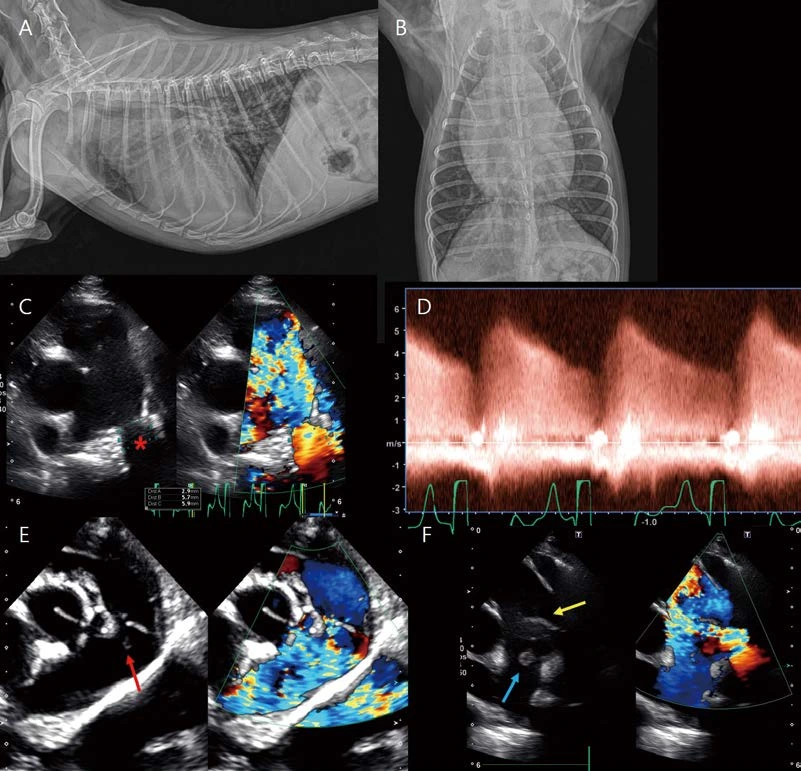

13살 수컷 26.5kg Golden retriever가 급성 기력저하로 내원하였습니다. 심한 노력성 호흡 상태에 혈압은 80mmHG였습니다. 흉부방사선 검사에서 폐야 전반에 걸친 작은 연조직 밀도 결절성 음영이 관찰됩니다(A, B). 심장은 globoid cardiomegaly with sharp contour를 보입니다(A, B). 폐초음파에서 폐전이가 고려되는 결절성 음영이 관찰됩니다(C). 심초음파에서 다량의 심낭수가 관찰되며(D, *), 이로 인한 cardiac tamponade(우심실, 우심방 collapse, CVC plethora, 소량의 복수)가 관찰됩니다. 일반적으로 스캔하는 Right parasternal four chamber long axis view, short axis view에서는 종괴 음영이 관찰되지 않으나, oblique로 right auricle을 스캔하면 right auricular wall 내외로 bulging된 결절성 종괴 음영을 찾을 수 있습니다(E, F). 이 환자는 심낭수 천자 및 세포학적 검사에서 primary cardiac hemangiosarcoma로 확인되었습니다. Hemangiosarcoma는 우심방, 우심이에서 잘 발생하는데, 심초음파에서 right auricle 병변은 놓치기가 쉽습니다. 심낭수가 있을 경우에는 스캔이 잘 되는 편이나, 심낭수가 없을 경우 right auricle 또는 left auricle 병변을 간과하기 쉬우므로 심초음파 스캔 시 주의가 필요합니다.